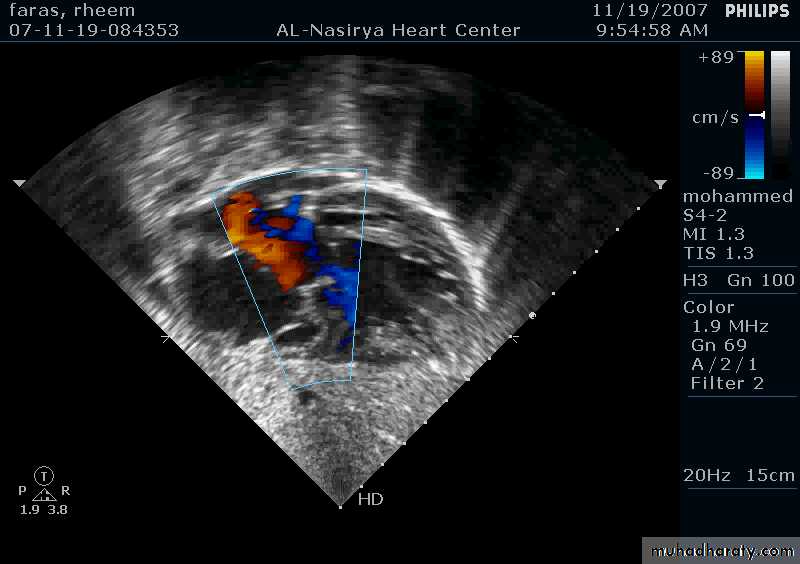

Ostium Primum ASD

37

38

33Echocardiography & TEE

Shows the size of the defectThe direction of blood flow

The pulmonary artery pressure34